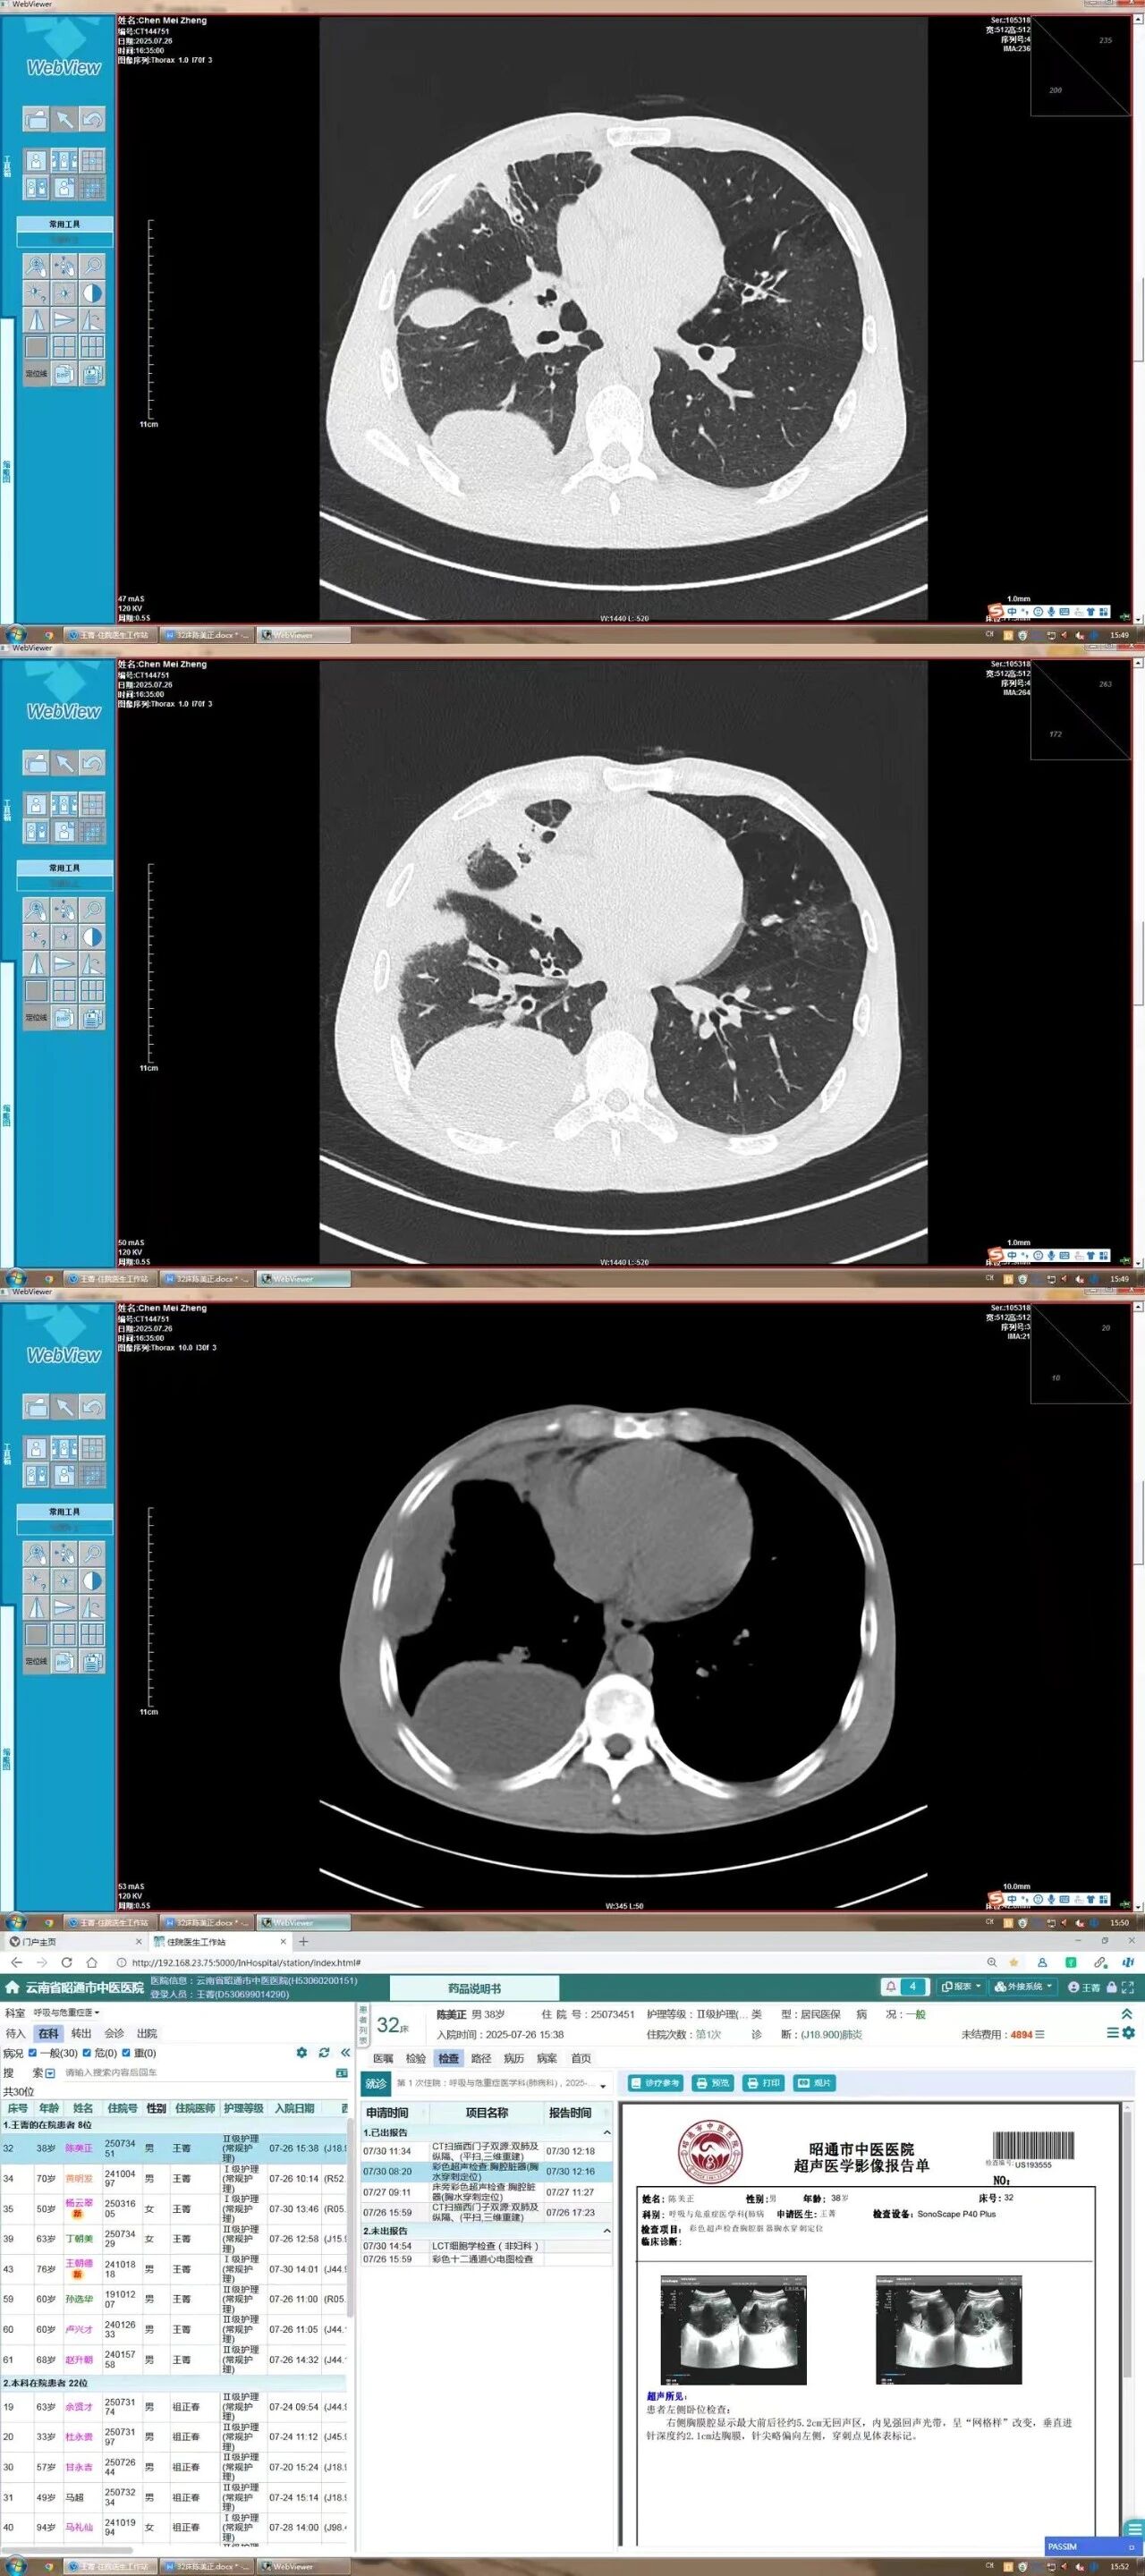

患者因咳嗽、咳痰、喘息乏力一周入院,CT检查显示其右侧胸腔存在大量包裹性积液且胸膜增厚粘连,传统穿刺引流困难。在我院建站专家——云南大学附属医院邢西迁主任的现场指导下,手术团队在局麻下利用内科胸腔镜精准操作,成功吸出大量脓性积液并送检,同时解除了胸膜粘连,患者术后恢复良好。